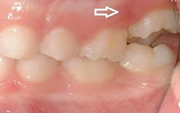

Esimeste molaaride (purihammaste) lõikumine. 1. molaaride ektoopilise lõikumise jälgimine. Ülemised ja alumised esimesed purihambad e. molaarid lõikuvad orienteeruvalt6-7-aastaselt piimahammaste rea lõppu. Enamasti lõikuvad samanimelised jäävhambad paaridena. Normaalne lõikumise Loe edasi »

Sümptomid:

- valehambumus (18)